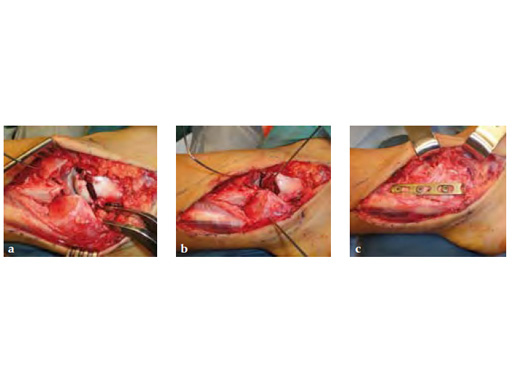

Fig 2ac Intraoperative images.